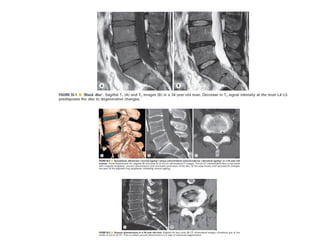

The spine is made up of vertebrae separated by intervertebral discs that allow movement and provide shock absorption. Diagnostic imaging plays an important role in evaluating the spine for conditions like fractures, disc herniations, spinal stenosis, and tumors. Imaging modalities like X-rays, CT scans, MRI, and bone scans can detect abnormalities and aid physicians in diagnosing and treating various spinal disorders.